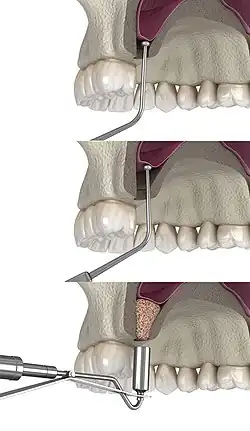

Sinus lift surgery, 3D Illustration

1) Edentulous area of two missing teeth is being prepared for future placement of dental implants with a lateral window sinus lift; incisions into the soft tissue are shown here.

2) The soft tissue is flapped back to expose the underlying lateral wall of the left maxillary sinus.

3) The bone has been removed with a piezoelectric instrument, exposing the underlying Schneiderian membrane, which is the lining of the maxillary sinus cavity.

4) Through careful instrumentation, the membrane is peeled from the inner aspect of the sinus cavity.

5) The membrane has been reflected from the internal aspect of the inferior portion of the sinus cavity; one can now visualize the bony floor of the sinus cavity without its lining membrane (note the triangular ridge of bone within the sinus, known as an Underwood's septum).

6) The newly formed space within the bony cavity of the sinus, yet inferior to the intact membrane, is grafted with human cadaver allograft bone. The floor of the sinus will now be roughly 10mm or larger than before, providing enough room to place dental implants into the edentulous site.

The procedure is performed intraorally, where the surgeon makes an incision into the gum. Once the incision is made, the surgeon then pulls back the gum tissue, exposing the lateral bony wall of the sinus. The surgeon then creates a "window" into the sinus, exposing the Schneiderian membrane. The membrane is separated from the bone, and bone graft material is placed into the newly created space. The gums are then sutured closed, and the graft is left to heal for 4 to 12 months.[8]